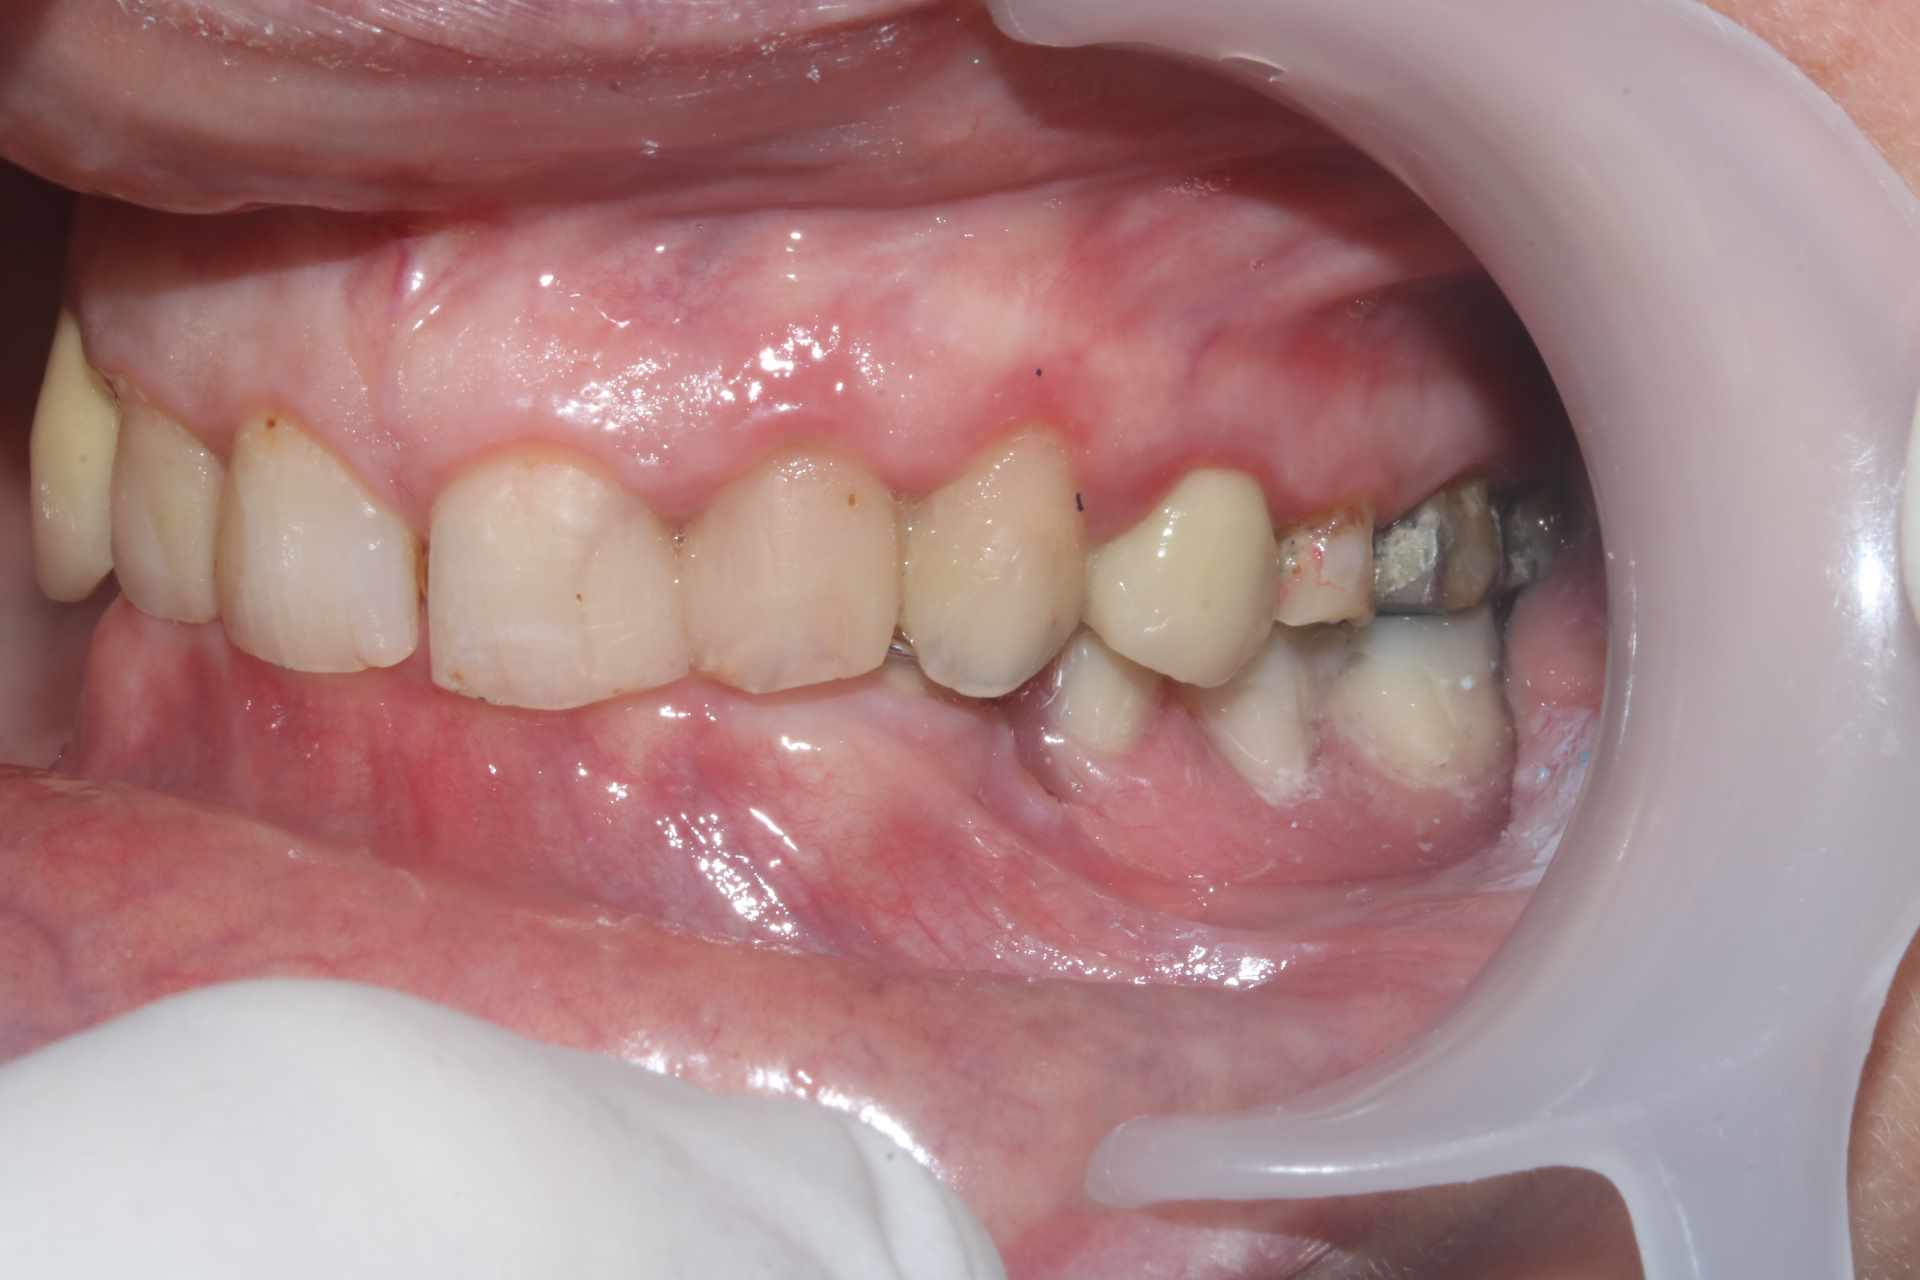

La patiente venait pour 34 35 descellées et 13 mobile. J'en suis encore au stade on traite les urgences avant de s'attaquer vraiment au cas. Vous voulez pas me donner un coup de main ? je ne sais pas trop par ou commencer !

On a une classe 2 2 majeure. ultra verrouillée. Je ne vois pas comment m'en sortir sans augmenter la DV qui a été malmenée par les soins et couronnes diverses a peu près tous en sous occ à mon avis sauf la 13 qui a explosé.

A mon avis on va être bon pour (re)faire les couronnes sur 4-5-6 de chaque coté (+ la 7 qui reste) qui semblent bien basses. Je pense qu'on a une perte de 1 à 2 mm à vu de nez en comparant avec les antérieures. Sauf la 24 qui a l'air à peu près OK en terme de DV mais on peut refaire quand même.

Oui la couronne sur sur 13 c'est une honte, volumineuse et beaucoup trop longue. Je suspecte une couronne faite avec un mordu unilatéral pour expliquer une telle aberration.

Sur 34 35 il y avait des couronnes jumelées qui se sont descellées peu après que la 13 se descellée / fracture.